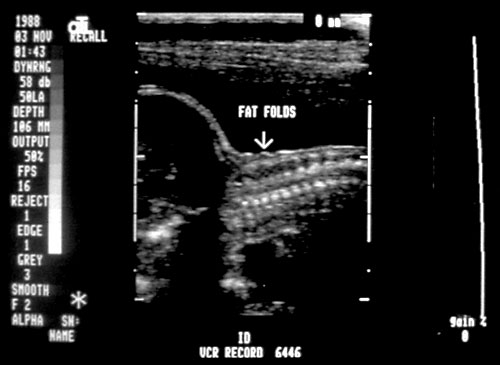

Normal cervical spine at 18 weeks (1). Another normal sagittal view of cervical spine seen in third trimester with folds of fat seen (2). Normal thoracic spine at 18 weeks (3). Normal sagittal view of lumbosacral spine at 18 weeks (4). Normal transverse view of lumbosacral spine at 18 weeks (5). - Extremities (hands/feet)